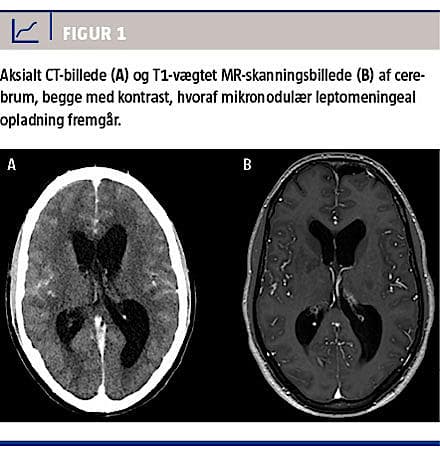

Paraklinisk havde patienten anæmi og forhøjet sænkningsreaktion. Der blev foretaget en PET-CT, som viste mediastinal lymfadenopati, og der blev derfor også foretaget endobronkial ultralydskanning med bioptering af de pågældende lymfeknuder. Under indlæggelsen blev patienten tiltagende udadreagerende. En CT af cerebrum viste hydrocefalus, periventrikulært ødem og meningeal opladning (Figur 1).

Billeddiagnostik (CT/MR-skanning af cerebrum) kan vise hydrocefalus (ca. 75%), parenkymlæsioner (15-30%) og meningeal fortykkelse (ca. 40%) [2]. CSV har ofte højt proteinindhold og lavt glukoseindhold samt pleocytose, oftest med mononukleær overvægt. Antituberkuløs behandling skal påbegyndes, så snart der er klinisk mistanke om TBM, og må ikke forsinkes af, at man afventer svar på mikroskopi, dyrkning, polymerasekædereaktion eller anden diagnostik.